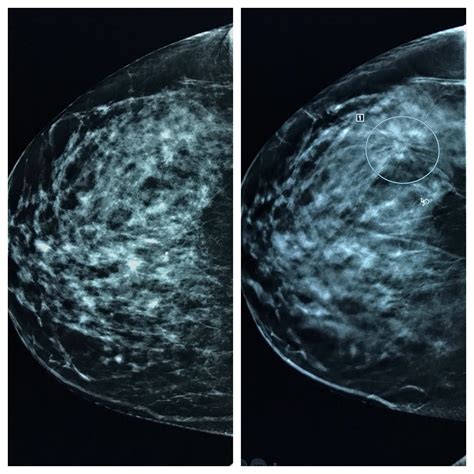

It is important not to panic if you are asked to return for additional images. Even if your normal mammogram images were overall clear, a radiologist might request a "diagnostic mammogram" or an ultrasound if they see something that is not clearly benign but is likely harmless. This often happens because:

- The initial images were blurry or had movement artifact.

- There was a small area of overlapping tissue that looked suspicious but was actually just normal anatomy.

- You have a new baseline, and the radiologist wants a more detailed view of a specific area to be absolutely sure.

Diagnostic imaging acts as a safety net, ensuring that you receive the most accurate diagnosis possible. Most call-backs do not result in a diagnosis of cancer; rather, they serve as a way for the medical team to get a better look at healthy, albeit complex, breast structures.